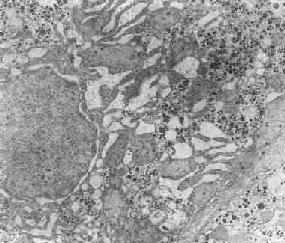

在生理狀態(tài)下,隨著細(xì)胞功能的升降,光面內(nèi)質(zhì)網(wǎng)(SER)的數(shù)量也呈現(xiàn)相應(yīng)改變。但亦可出現(xiàn)完全相反的情況,例如在某些疾?。ㄈ缬倌懀r(shí),從形態(tài)結(jié)構(gòu)上看,肝細(xì)胞光面內(nèi)質(zhì)網(wǎng)顯著增生(下圖),但其混合功能氧化酶的活性反而下降,這實(shí)際上是細(xì)胞衰竭的表現(xiàn)。

許 多成癮藥物和嗜好品如巴比妥類、吸毒、嗜酒等,可導(dǎo)致肝細(xì)胞光面內(nèi)質(zhì)網(wǎng)的增生,長期服用口服避孕藥、安眠藥、抗糖尿病藥等也能導(dǎo)致同樣后果。在HBsAg 陽性肝炎時(shí),肝細(xì)胞內(nèi)光面內(nèi)質(zhì)網(wǎng)明顯增生,在其管道內(nèi)形成HBsAg。由于光面內(nèi)質(zhì)網(wǎng)的大量增生,這種肝細(xì)胞在光學(xué)顯微鏡下呈毛玻璃外觀,故有毛玻璃細(xì)胞 之稱,并可為地衣紅(orcein)著染。

肝細(xì)胞粗面內(nèi)質(zhì)網(wǎng)擴(kuò)張